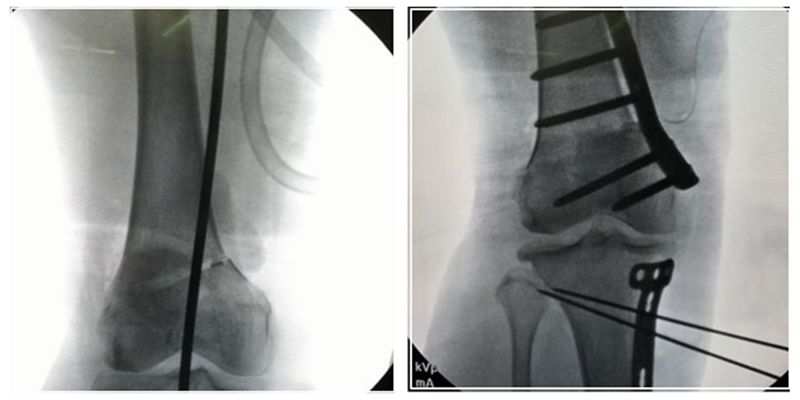

术后影像